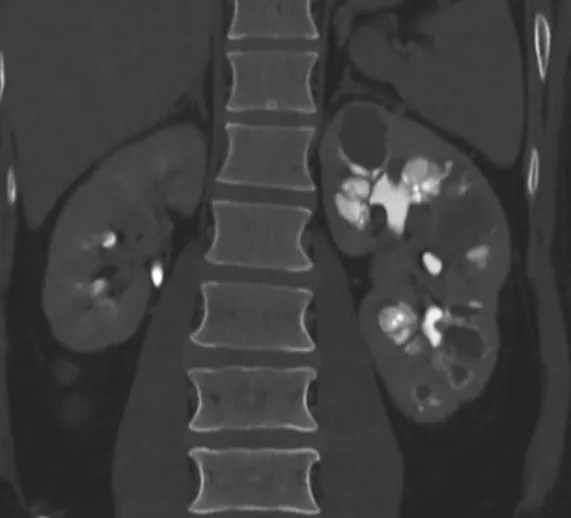

Hematúria e anormalidades em tomografia